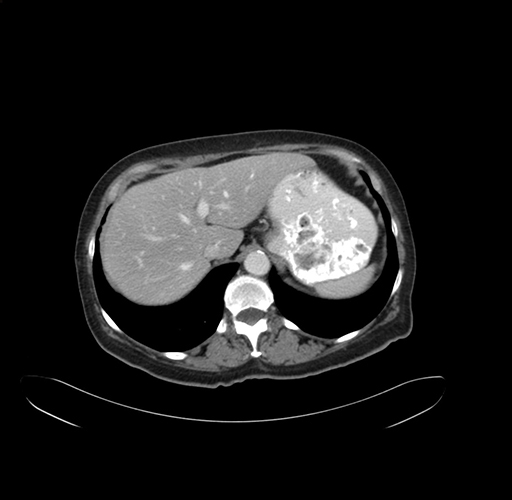

Pre-Chemo: Axial Venous